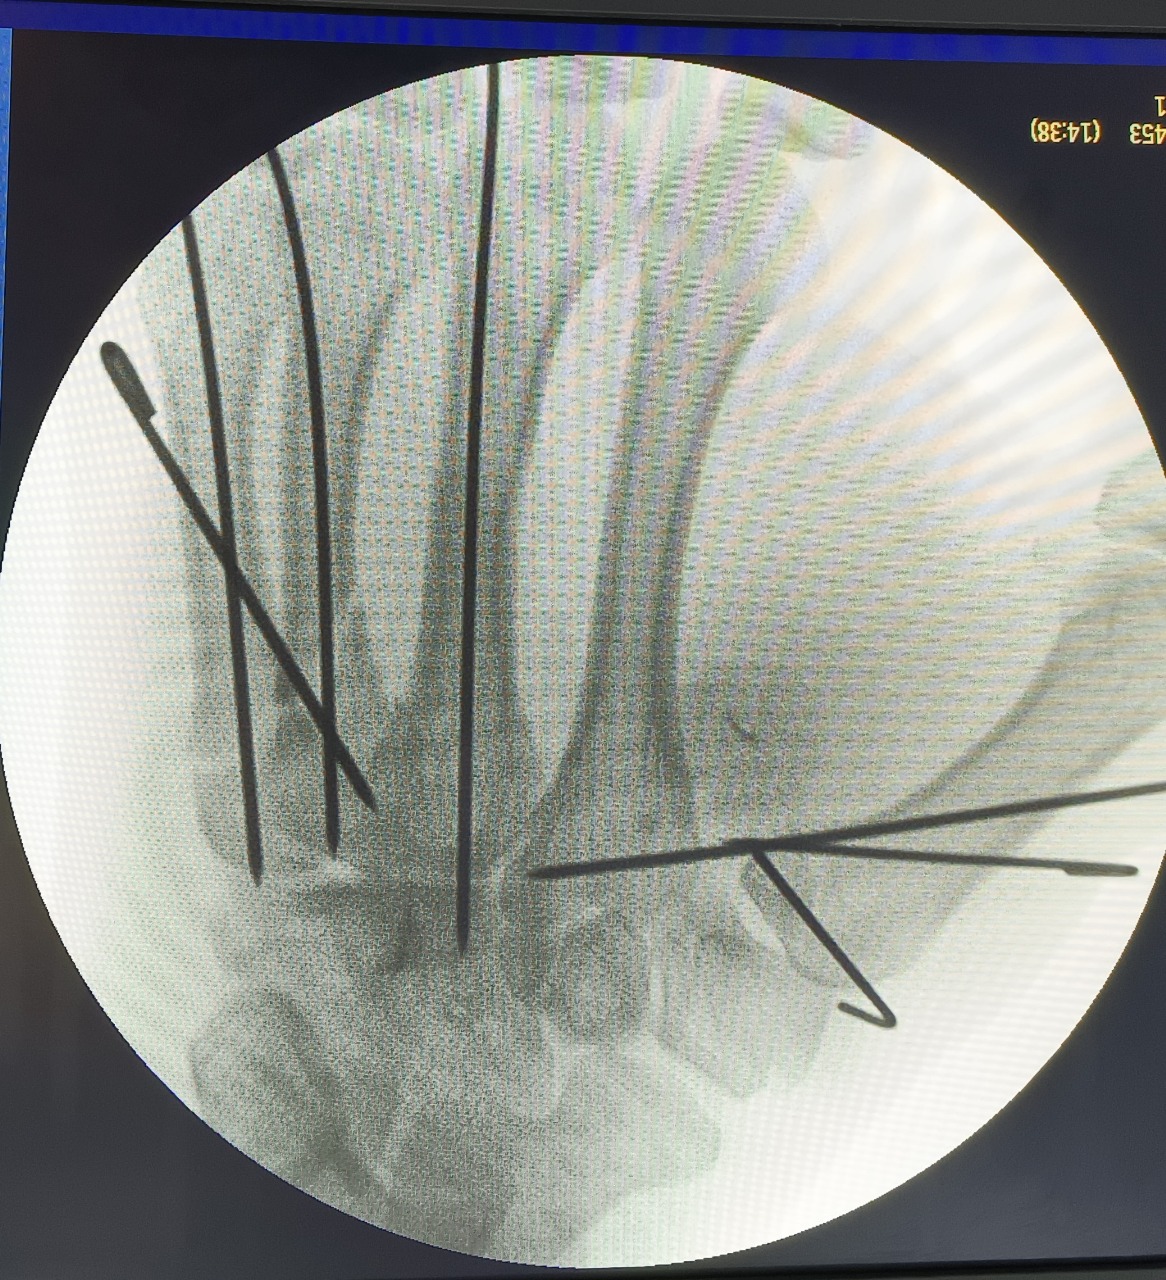

Hand Surgery

Expert surgical care restoring hand function, correcting deformities, and treating injuries

Trauma Reconstruction

Expert reconstruction for injuries caused by accidents, fractures, and soft tissue damage.